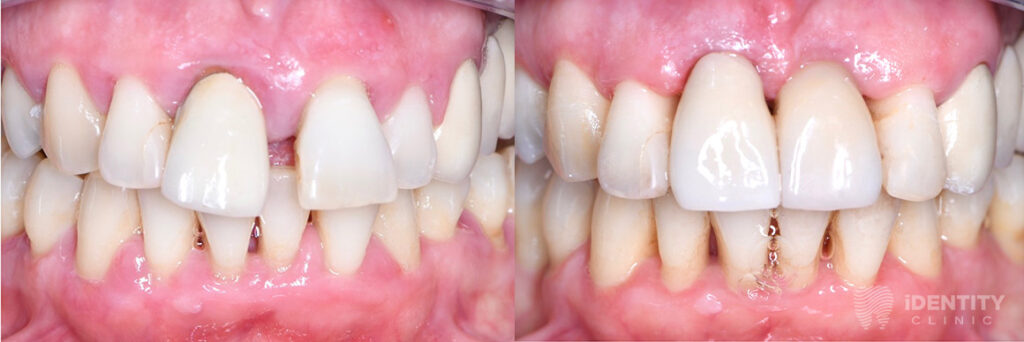

Reménytelen prognózisú 21 (bal felső első) fog eltávolítását követően a nagymértékű csonthiány miatt azonnali csontpótlást végeztünk a páciens saját csontja, illetve kötőszövete segítségével (alveolus prezerváció). Ennek 4 hónapos gyógyulási idejére az eltávolított 21 fog koronáját visszasíneztük a szomszédos fogakhoz. A teljeskörű parodontális terápiát mindeközben elvégeztük.

A gyógyulási időt követően implantátum beültetésével pótoltuk a 21 fogat, melyre az ezt követő 3 hónapos gyógyulási időre (az implantátum csontos gyógyulásának ideje) ideiglenes koronával láttunk el, mely már nagymértékben javította a páciens esztétikai kívánságát.

A teljes gyógyulási idő leteltével az implantátumot, illetve a jobb felső 1-es fogat leplezett cirkóniumvázas szólókoronákkal láttuk el.

Előtte-utána